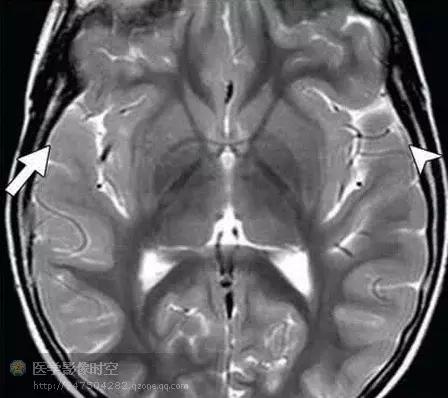

一侧巨脑症具有典型的磁共振成像特征。最显著的特征是单侧皮层增厚,累及部分或者全部大脑半球。受累大脑半球也显示继发于髓鞘化过度的单侧白质改变,这取决于具体的髓鞘化程度。也可以单侧基底节和嗅束的错构瘤样受累。另外,也常见单侧侧脑室增大。神经影像学新技术例如扩散张量成像和MR-PET融合图像也可以提供更多的认识。扩散张量成像和纤维示踪图提示异常的大脑半球过度髓鞘化,表现为局部的水分子扩散的各向异性不对称性升高(图9b,c)。发作期MR-PET融合图像可以清晰显示受累大脑半球的不对称性高代谢区。

图9a横断T2WI显示巨脑回和右侧皮层增厚(箭头)以及异常的邻近白质低信号(箭)

图9b横断扩散张量成像显示右侧前额叶髓鞘化程度过高(箭),与异常的T2WI高信号相对应。

图9c纤维示踪图显示右侧大脑半球较多侧神经纤维束更多。

图9d横断发作期MR-PET融合图像显示右侧额叶在癫痫发作期间为高代谢区(箭)